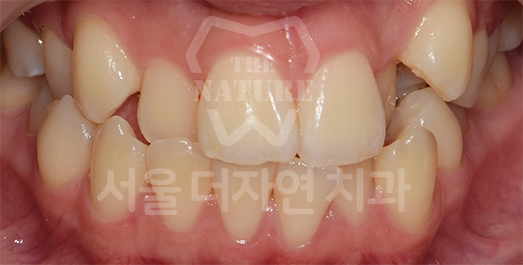

덧니 교정 Solution

덧니는 치아가 올라올 공간이 부족하여

제자리에 올라오지 못하는 상태를 말합니다.

덧니를 오랫동안 방치할 경우 칫솔질이 제대로 되지 않아

치아 사이에 음식물이 잘 끼고, 충치가 생길 위험이 큽니다.

또한 치주 질환의 원인이 되므로

교정치료를 통해 개선하는 것이 바람직합니다.

AFTER: 2023.02.02